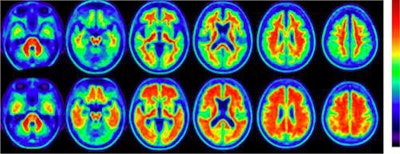

Italian researchers may have discovered a reliable clinical marker that links levels of amyloid deposits in the brain with increased episodic memory impairment through florbetaben-PET imaging, according to a study published online on 22 September by the European Journal of Nuclear Medicine and Molecular Imaging.

Researchers found that a standardized uptake value ratio (SUVr) of 1.3 for florbetaben tracer uptake distinguishes between low and high amyloid retention. Subjects above that SUVr threshold exhibited significantly poorer cognitive and episodic memory skills than individuals with amyloid deposition below that benchmark.

"By means of florbetaben-PET imaging we were able to discriminate two amnesic mild cognitive impairment subgroups with significantly different amyloid retention levels," wrote the researchers led by Dr. Andrea Ciarmiello from the nuclear medicine department at S. Andrea Hospital in La Spezia. "The elevated levels of florbetaben uptake were found to be associated to cognitive decline, in particular to a significantly greater decline in episodic memory."

In this prospective study, 63 subjects underwent PET/CT scans (Discovery 710, GE Healthcare) approximately 86 (± 8) minutes after injection of 306 (± 29) MBq of florbetaben (Neuraceq, Life Medical Imaging). The researchers also used the Mini-Mental State Examination (MMSE) to determine a subject's cognitive abilities. The standard MMSE score above 24 was an indication of mild cognitive impairment and scores below 24 as cognitively normal.